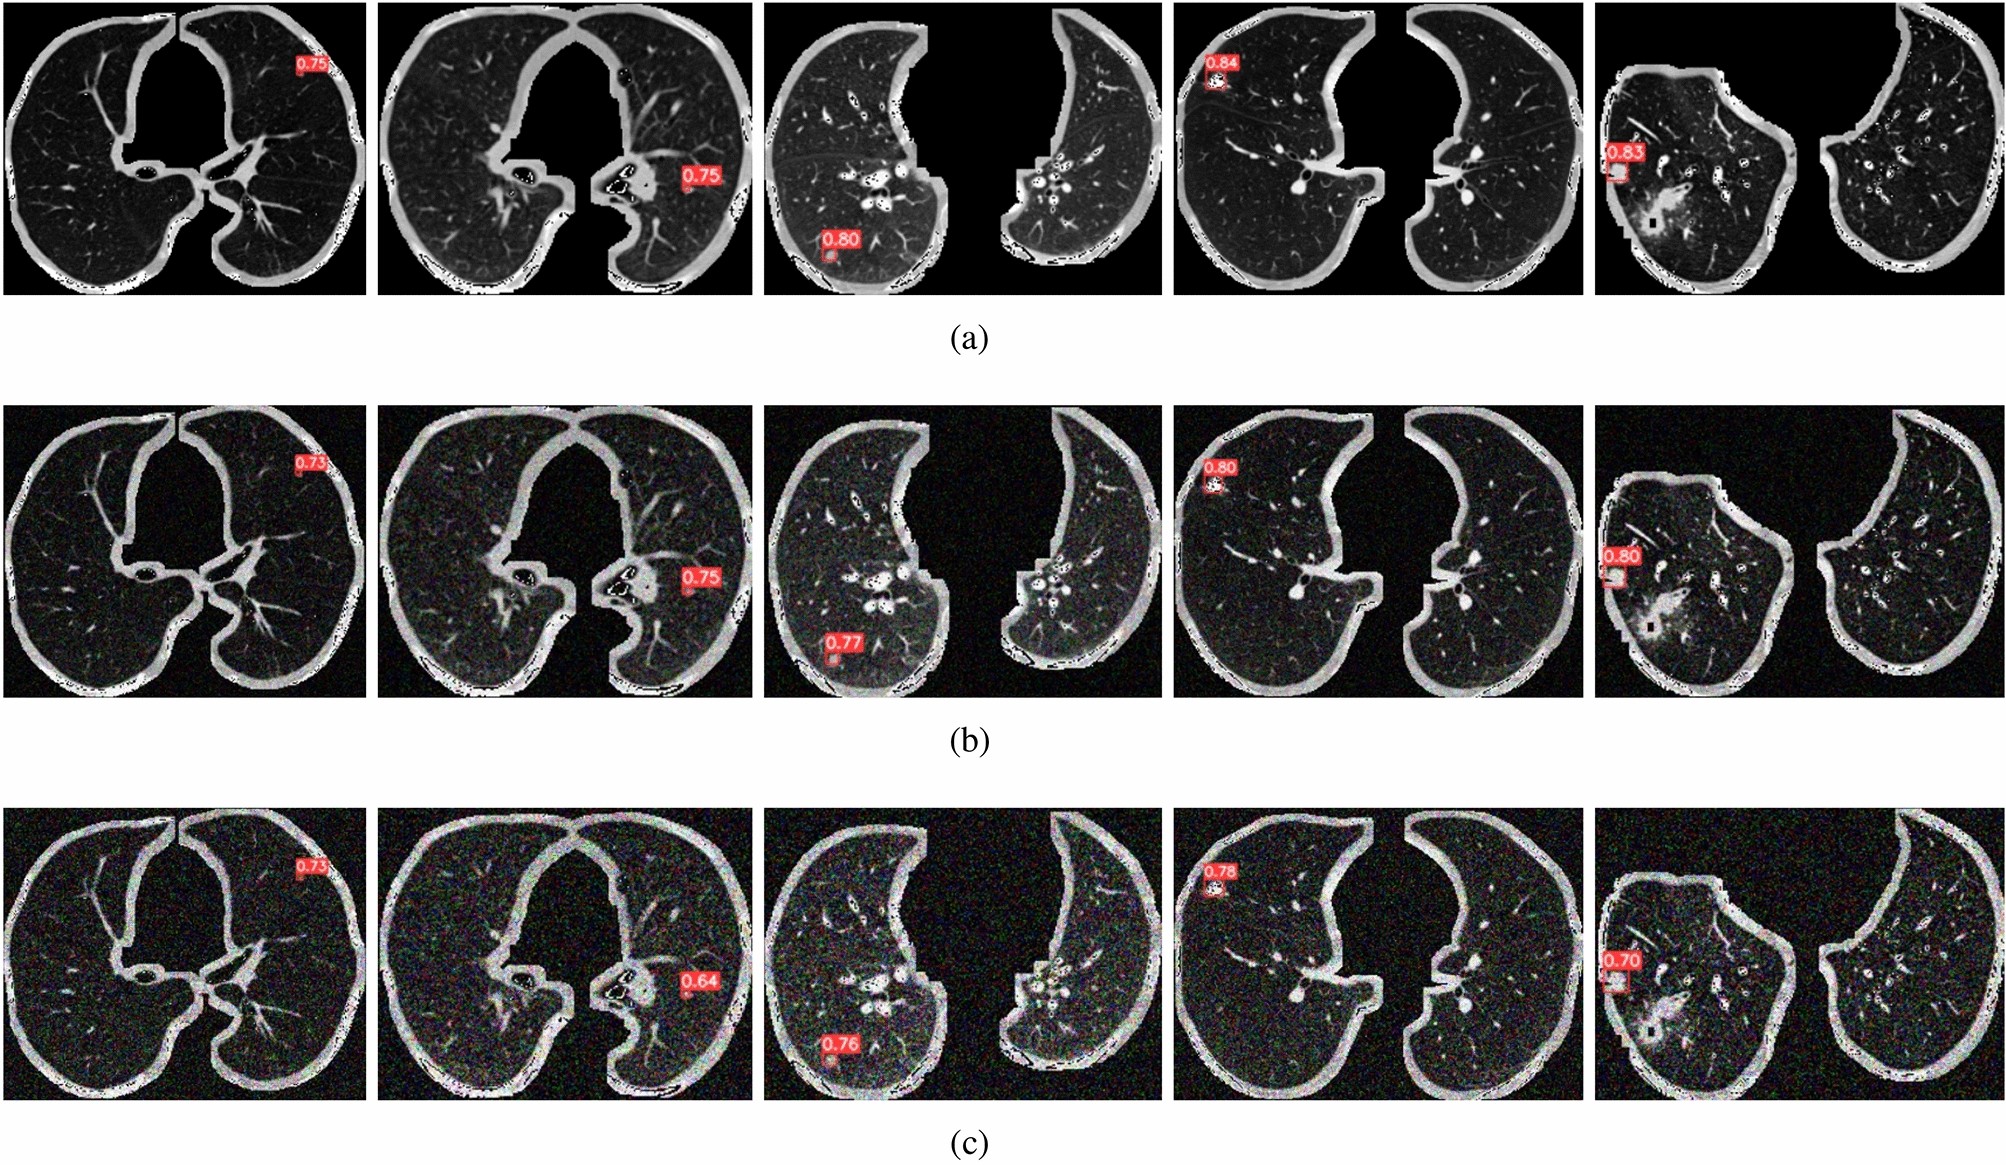

Figure 8

The response of LN-DETR to varying levels of noise. LN-DETR maintains a relatively stable accuracy across different noise levels.